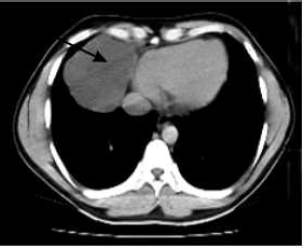

Se realiza tomografía axial computarizada (TAC) simple de tórax, donde se observa la presencia de una masa en el ángulo cardiofrénico derecho, con densidad de 3 UH, que mide 8 cm y provoca ligero desplazamiento del mediastino, compatible con un quiste celómico del pericardio (Fig. 2).